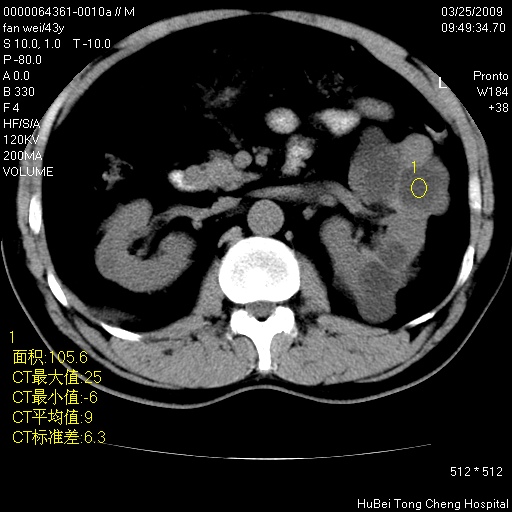

患者 男,43岁。左侧腰部不适两天。平素健康。无家族遗传病史。

腹部彩超提示:1)轻度脂肪肝。2)左肾多发囊性占位性病变;建议行进一步检查。

临床诊断:左肾多发囊性占位性病变,性质待定(多发肾囊肿?)。

双肾ct轴位平扫+增强扫描(层厚10mm,螺距1.0,重建间隔10mm),图像如下:

多囊肾的影像诊断标准:有阳性家族史,年龄<30岁,单侧或双侧肾脏有两个肾囊肿;30~59岁,两侧肾脏各有两个肾囊肿;60岁以上,每侧肾脏有4个囊肿。敏感性和特异性达86%和80%。

此病例影像诊断符合,要结合家族史,腰痛、血尿、尿路感染史,有无高血压等综合判断,如无相应的临床症状,本身病变也无意义了(个人观点)